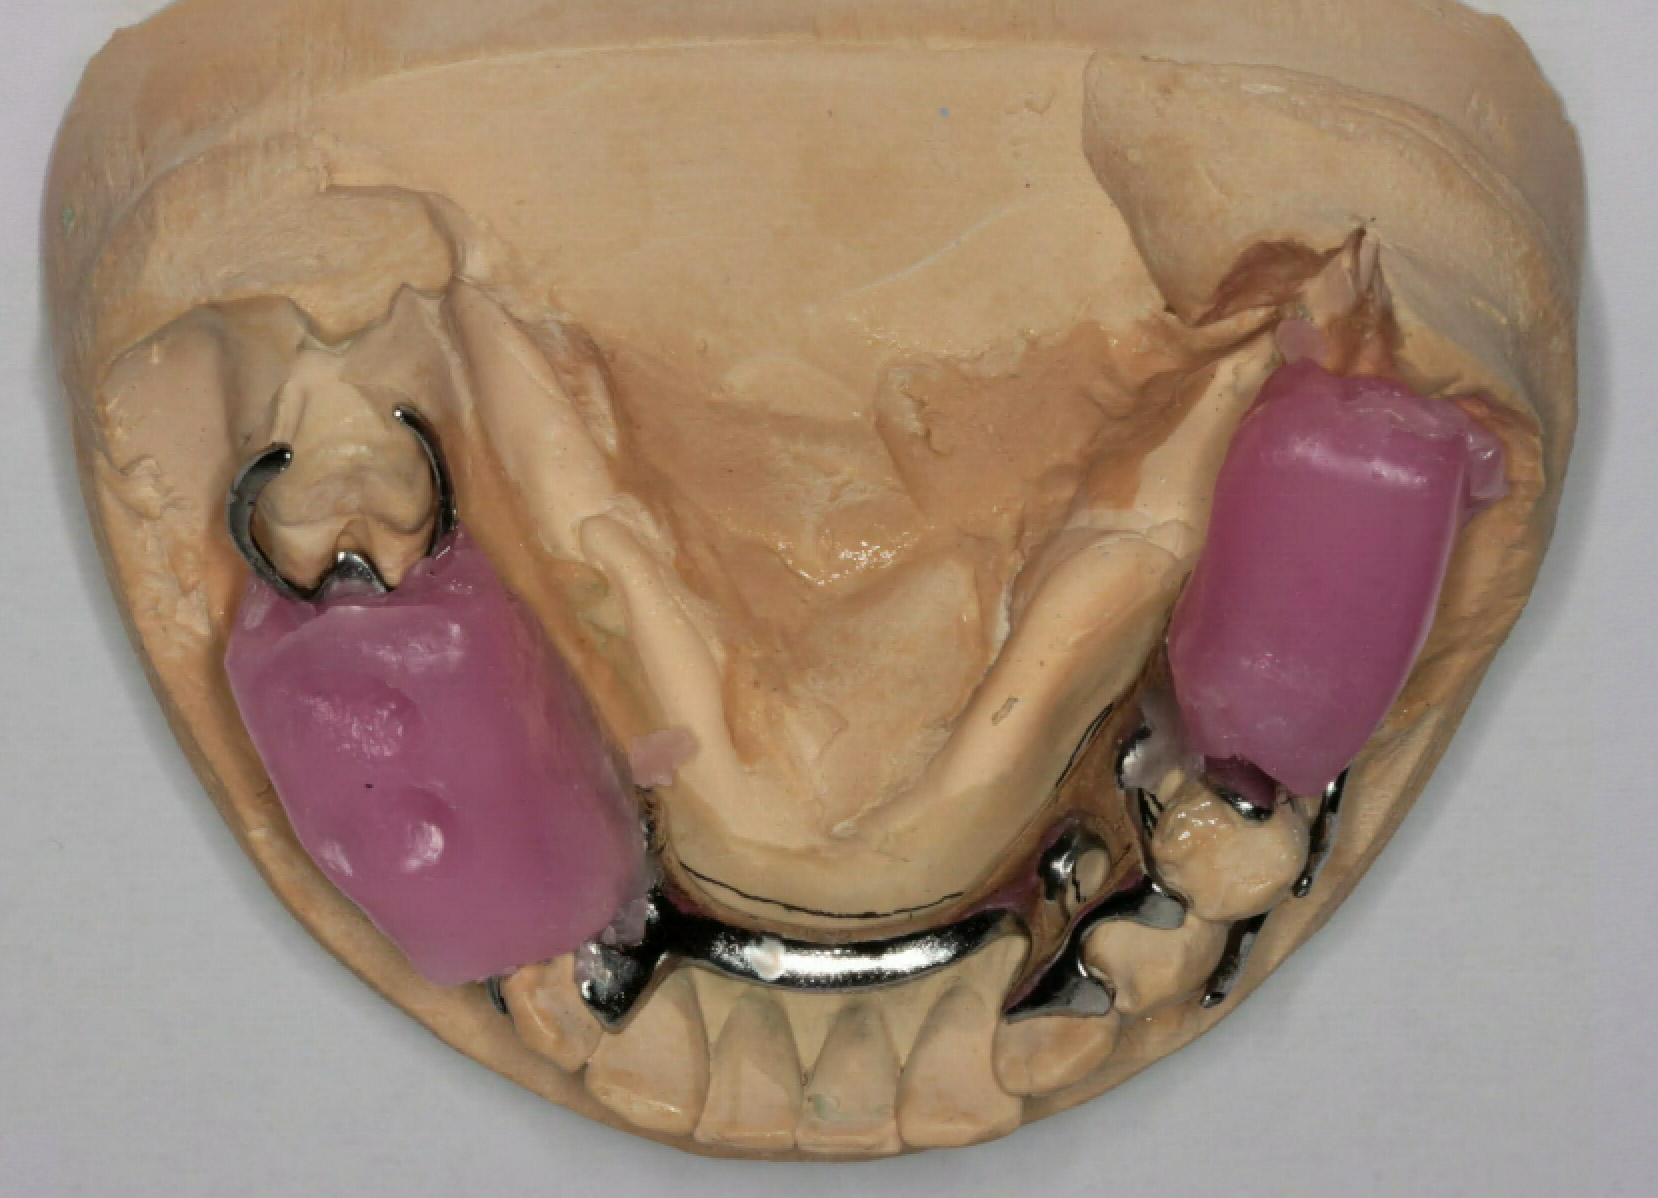

Start of the dentures

• Prepared customed trays. Border moulding and PVS final impressions for making of metal framework.

• Mouth modifications (created occlusal/cingulum rests and guiding planes for additional support)

• 47 (US # 31) has a questionable prognosis due to high restored tooth and 2 additional class 5 caries mesio-distally. We decided to design the partial denture so that we could add a denture tooth if the patient

• Metal framework try in, occlusal rim and bite registration, and selection of shade/shape of acrylic teeth for upper and lower partial dentures.